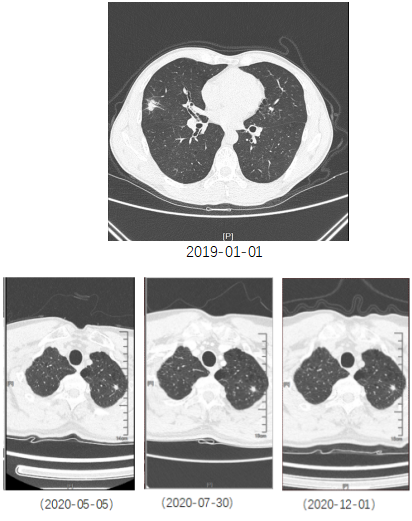

近日,我院呼吸与危重症医学科来了一个“老”病人。患者于2018年体检CT提示双肺多发结节、右肺中叶结节,大小约1.5*1.0cm,考虑恶性肿瘤的可能性大。去年,患者于全麻下行胸腔镜下肺肿瘤切除术(右),术后病理确诊为腺癌。经过4次化疗,并定期随访CT。去年5月份,从原先的6.89mm*5.3mm逐渐发展到了7.62mm*6.21mm。

经历波折,但是故事还远远没有结束。去年12月22日,患者行胸腔镜下左上肺肿瘤切除术,病理提示为“左上肺原位腺癌伴微浸润”。在随访过程中,发现患者右上肺的小结节的病灶密度增加了。这个病灶只有4.8*3.9mm,在未明确病灶是否是恶性的情况下,患者肺部已经经历过两次手术,接下来是否应该再次行手术?患者为此感到焦虑。对于患者来说,是个左右两难的大问题。带着这个困惑,患者来到我们医院。为进一步明确诊断,我们提出行磁导航气管镜检查,可以用最小的创伤来取得病理标本,避免再次手术带来的创伤和风险。